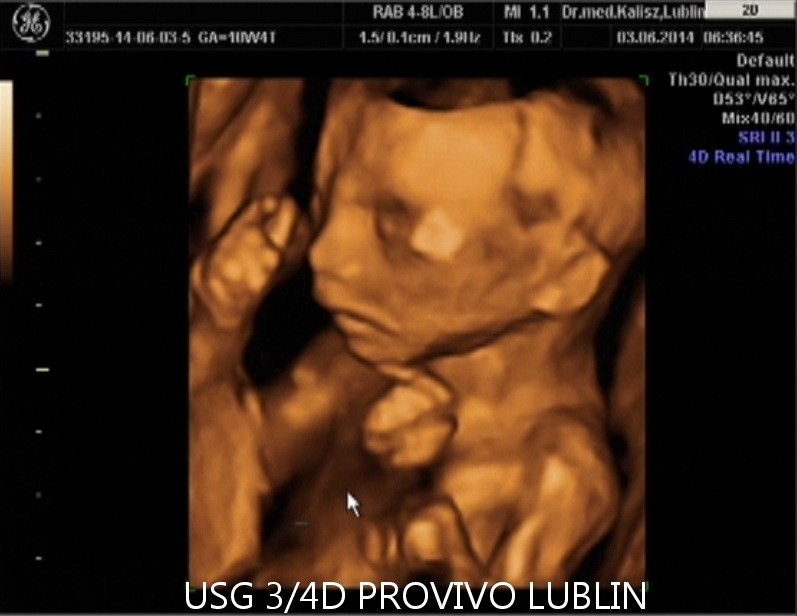

Urządzenia do USG 3D i 4D pokazują wyniki badania USG w sposób trójwymiarowy, dzięki czemu przyszli rodzice, zamiast jasnych i ciemnych plam na ekranie i zdjęciach, mogą zobaczyć swoje dziecko na żywo, zanim jeszcze pojawi się na świecie.

USG 4D pokazuje obraz podobny jak w przypadku badania 3D, z tą różnicą, że jest to obraz dynamiczny, który zmienia się w czasie rzeczywistym. Przypomina to nieco podgląd na żywo, jak gdyby w macicy była umieszczona kamera.

Przyszli rodzice zobaczą w ten sposób ruchy dziecka, a także mimikę jego twarzy. Dla większości par jest to niezwykle wzruszająca chwili, kiedy po raz pierwszy mogą na własne oczy zobaczyć własne dziecko.

W trakcie ciąży takie badanie może być wykonane między 11-14 tygodniem ciąży, a potem około 20 lub 30 tygodnia.